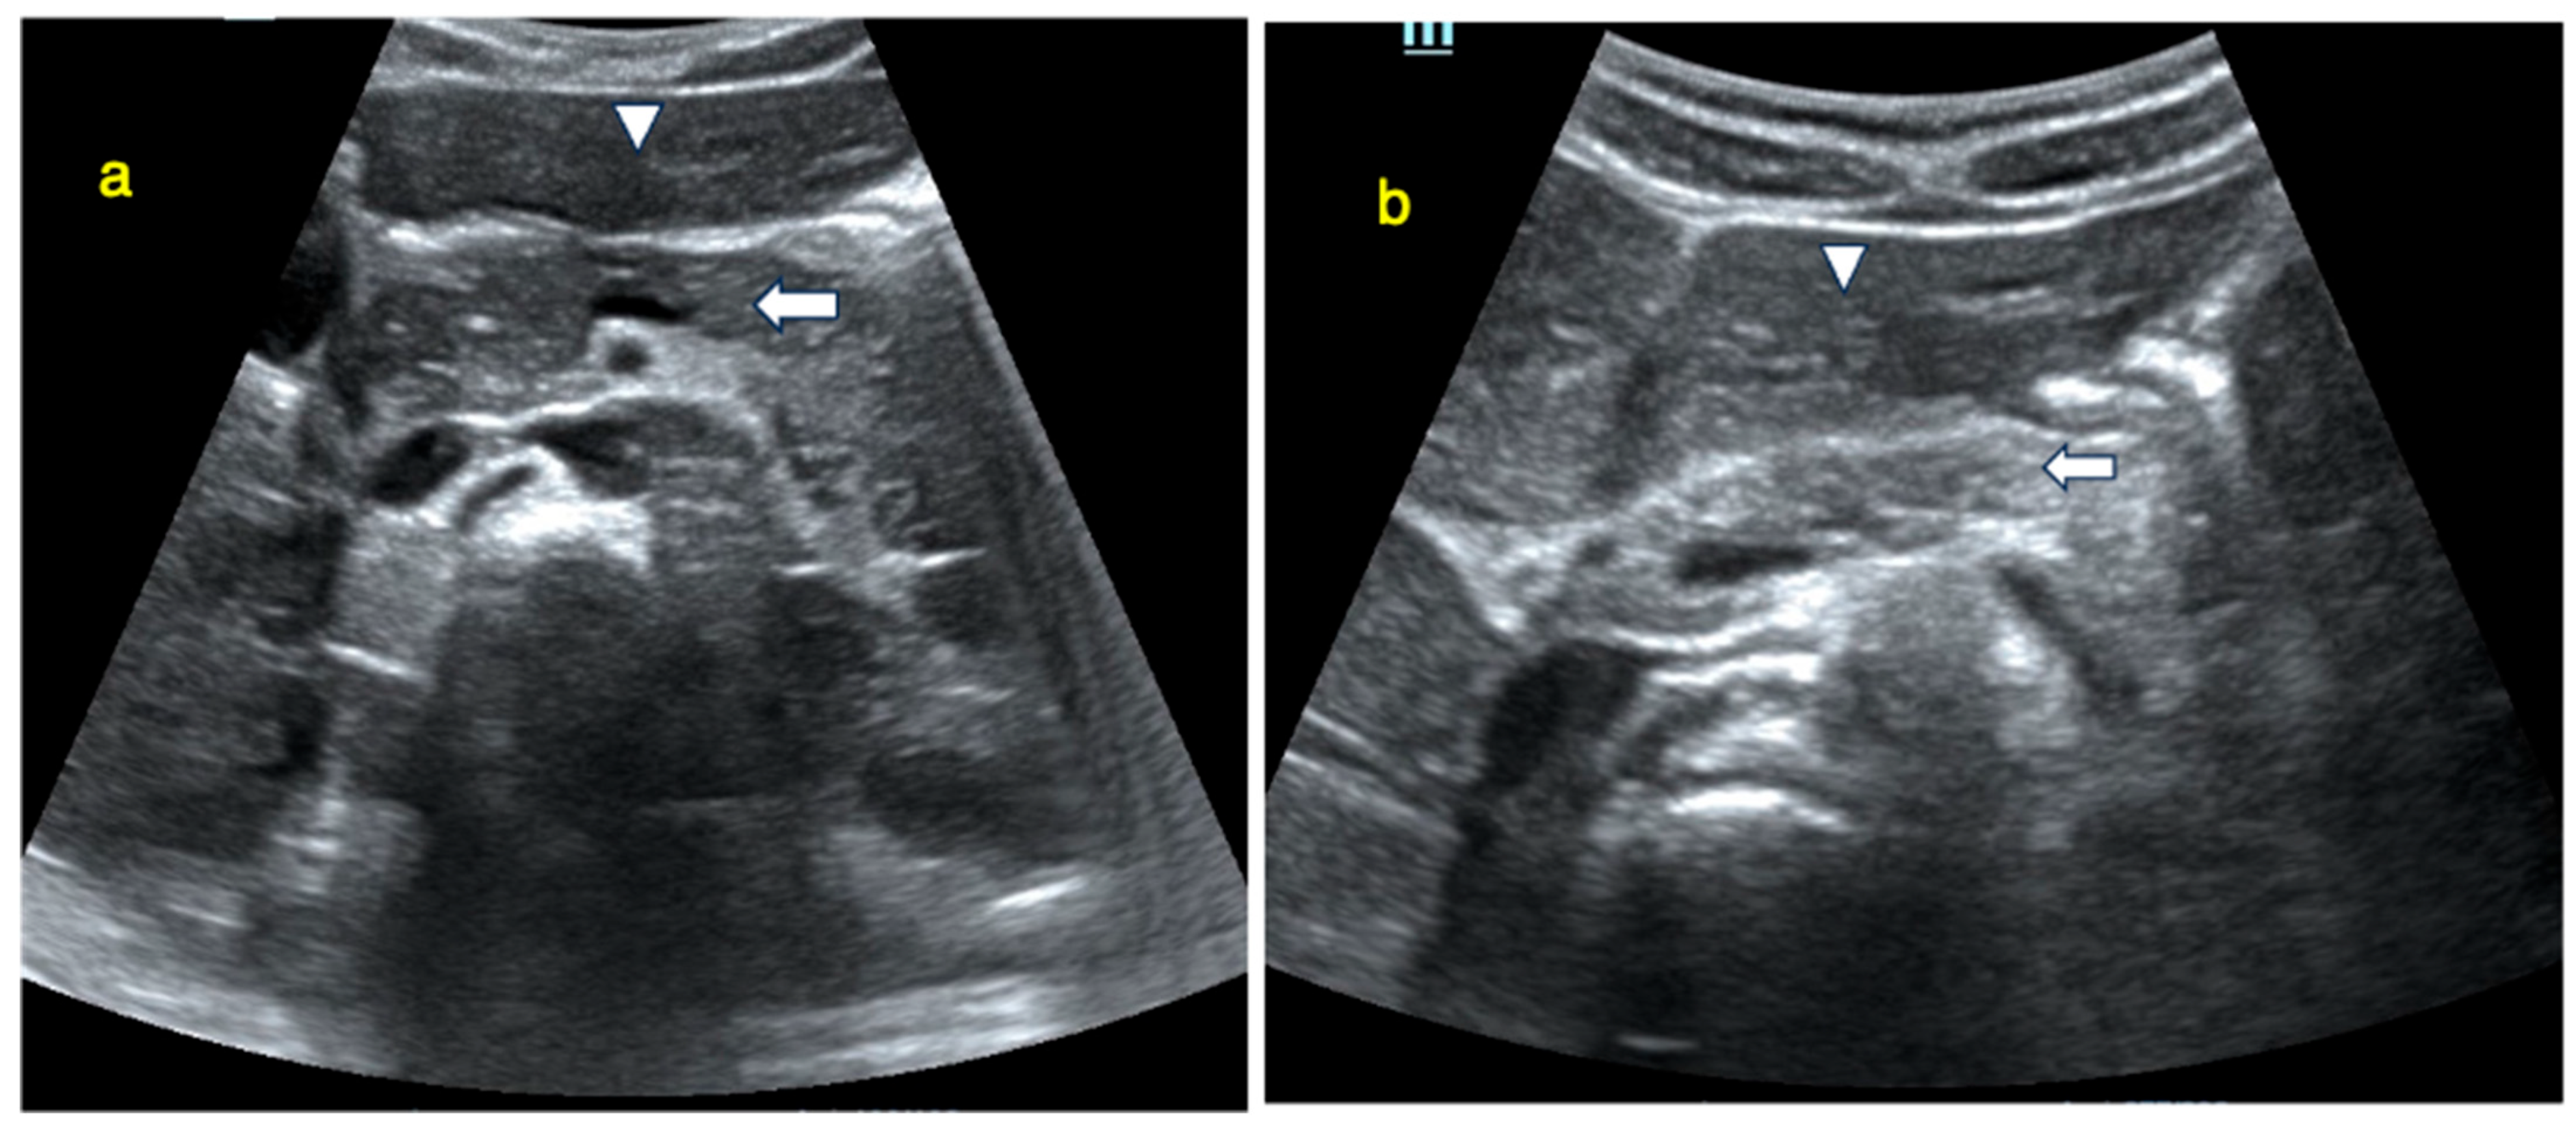

Ultrasonographic evaluations of the pancreas were performed within five days of T1DM diagnosis in metabolically stable patients who had initiated short- and long-acting conventional insulin treatment. Visualisations were performed by one experienced pediatric radiologist under the supervision of a senior pediatric radiologist using the LOGIQ S8 ultrasound system (General Electric Medical Systems, Milwaukee, WI, USA) equipped with a convex array transducer (1–6 MHz). To ensure reproducibility, all ultrasonographic assessments were performed using standardized scanning protocols under fasting conditions and with identical equipment and transducer settings. Measurements were obtained three times for each pancreatic segment (head, body, and tail), and the mean values were used for analysis to minimize intra-observer variability. Established pediatric pancreatic USG protocols were followed to ensure reliability [8,9]. A pancreatic image from a single participant, illustrating the head, body, and tail measurement locations, is presented in Figure 1.

Figure 1. Upper abdominal ultrasound. Pancreatic size measurements: 1 = head, 2 = body; tail shown in green. For each region, the measurement corresponds to the dotted line between the two “+” caliper marks—white “+” for head (1) and body (2), green “+” for tail.